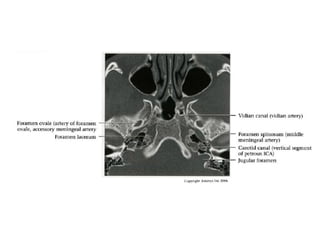

Overview

• Complex course with several vertical /

horizontal segments, 3 genus (one

petrous, two cavernous)

• Six intracranial segments (Cervical lCA =

C1):

- Petrous (C2), Lacerum (C3),

Cavernous (C4), Clinoid (C5),

Ophthalmic (C6), Communicating (C7)

Petrous (C2) segment

• Contained within carotid canal of temporal bone

- Surrounded by extensive sympathetic plexus

- Two C2 subsegments joined at genu

• Short vertical segment - anterior to internal jugular vein

(lJV)

• "Genu" (where petrous ICA turns anteromedially in front

of cochlea)

• Longer horizontal segment

- Exits carotid canal at petrous apex

- Branches

• Vidian artery (artery of pterygoid canal)

anastomoses with external carotid artery (ECA)

• Caroticotympanic artery (supplies middle ear)

Lacerum (C3) segment

• Small segment that extends from petrous

apex above foramen lacerum, curving

upwards toward cavernous sinus

• Covered by trigeminal ganglion

• No branches

Cavernous (C4) segment

• Three subsegments joined by two genus (knees)

- Posterior vertical (ascending) portion

- Posterior (more medial) genu

- Horizontal segment

- Anterior (more lateral) genu

- Anterior vertical (subclinoid) segment

• Covered by trigeminal ganglion posteriorly

• Abducens nerve (CN6) is inferolateral

• Major branches

- Meningohypophyseal trunk (arises from posterior

genu, supplies pituitary, tentorium and clival dura)

- Inferolateral trunk arises from horizontal segment,

supplies cavernous sinus (CS) dura / cranial nerves;

anastomoses with ECA branches through foramens

rotundum, spinosum, ovale